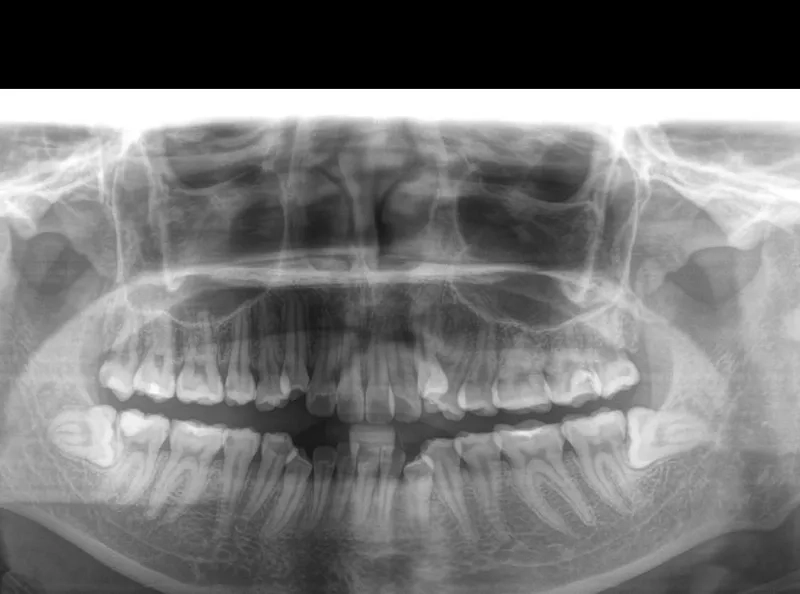

Chính vì là kẻ đến sau cùng, răng khôn thường không tìm được vị trí thuận lợi để mọc thẳng. Chúng phải tìm cách chen chúc, dẫn đến các tình trạng phổ biến như mọc lệch, mọc ngầm dưới nướu hoặc đâm ngang vào chiếc răng số 7 bên cạnh.

Khi răng khôn mọc lệch hoặc đâm ngang, nó sẽ trực tiếp húc vào chân răng số 7. Lực đẩy này diễn ra âm thầm nhưng mạnh mẽ, làm tiêu chân răng, gây sâu răng số 7 và có thể khiến chiếc răng này bị lung lay hoặc mất vĩnh viễn.

Xô lệch toàn bộ hệ thống hàm răng

Nguy cơ hình thành u nang xương hàm

Trong một số trường hợp răng khôn mọc ngầm hoàn toàn trong xương, các mô bao quanh răng có thể phát triển thành u nang.

Nếu không được phát hiện qua phim chụp X-quang, u nang này sẽ âm thầm phá hủy xương hàm, làm tổn thương các dây thần kinh và các răng xung quanh, gây ra những tổn thương nặng nề khó phục hồi.

- Phim chụp CT Cone Beam: Đây là bước chuẩn bị quan trọng nhất giúp bác sĩ xác định chính xác vị trí chân răng khôn và khoảng cách của chúng tới ống dây thần kinh hàm dưới trước khi thực hiện thao tác nhổ.